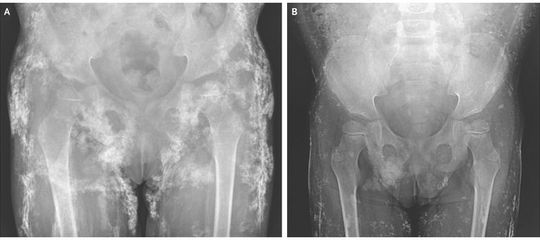

A 4-year-old girl with juvenile dermatomyositis was brought to the rheumatology clinic with a rash and limb weakness. She had had continuous disease activity without remission despite receiving treatment with multiple medications, including glucocorticoids, intravenous immune globulin, methotrexate, and cyclosporine, over a period of 3 years at another hospital. On physical examination, the patient had erythematous changes to the skin overlying the finger, knee, and elbow joints (findings consistent with Gottron’s sign), heliotrope rash around the eyes, proximal muscle weakness in the arms and legs, and diffuse, palpable subcutaneous nodules. A radiograph of the pelvis showed extensive calcification (Panel A). Magnetic resonance imaging of the thighs revealed muscle inflammation and calcinosis. The results of laboratory testing showed strong anti–nuclear matrix protein 2 (anti–NXP-2) autoantibody positivity, a finding associated with calcinosis in juvenile dermatomyositis. Given the patient’s refractory juvenile dermatomyositis and severe calcinosis, treatment with infliximab, thalidomide, and aluminum hydroxide was initiated. Two months after treatment, the patient had improved muscle strength and fading of the rash. At 9 months of treatment, a repeat radiograph showed that the calcinosis had decreased (Panel B).